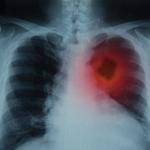

Болката в гърдите е сред най-разпространените симптоми на рак на белите дробове. И когато се смеем, тя се влошава. Това от своя страна може да е индикация за запушване в белите дробове - натрупване на течност, подути лимфни възли и оток. Експертите допълват, че болката може да се влоши и при дълбоко дишане и кашлица.